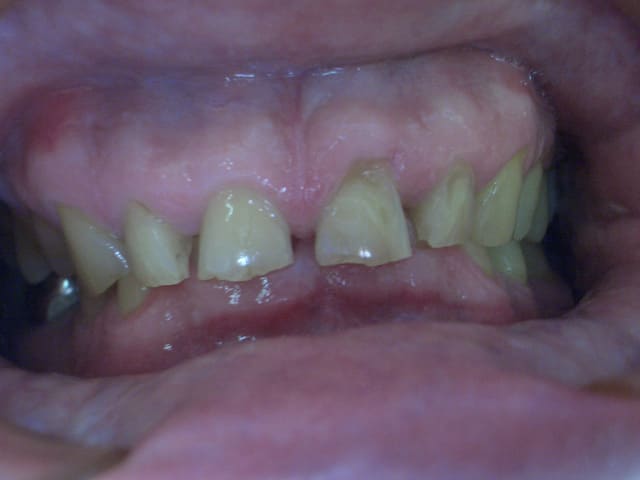

Occl initial hcvx7i - Eugenol